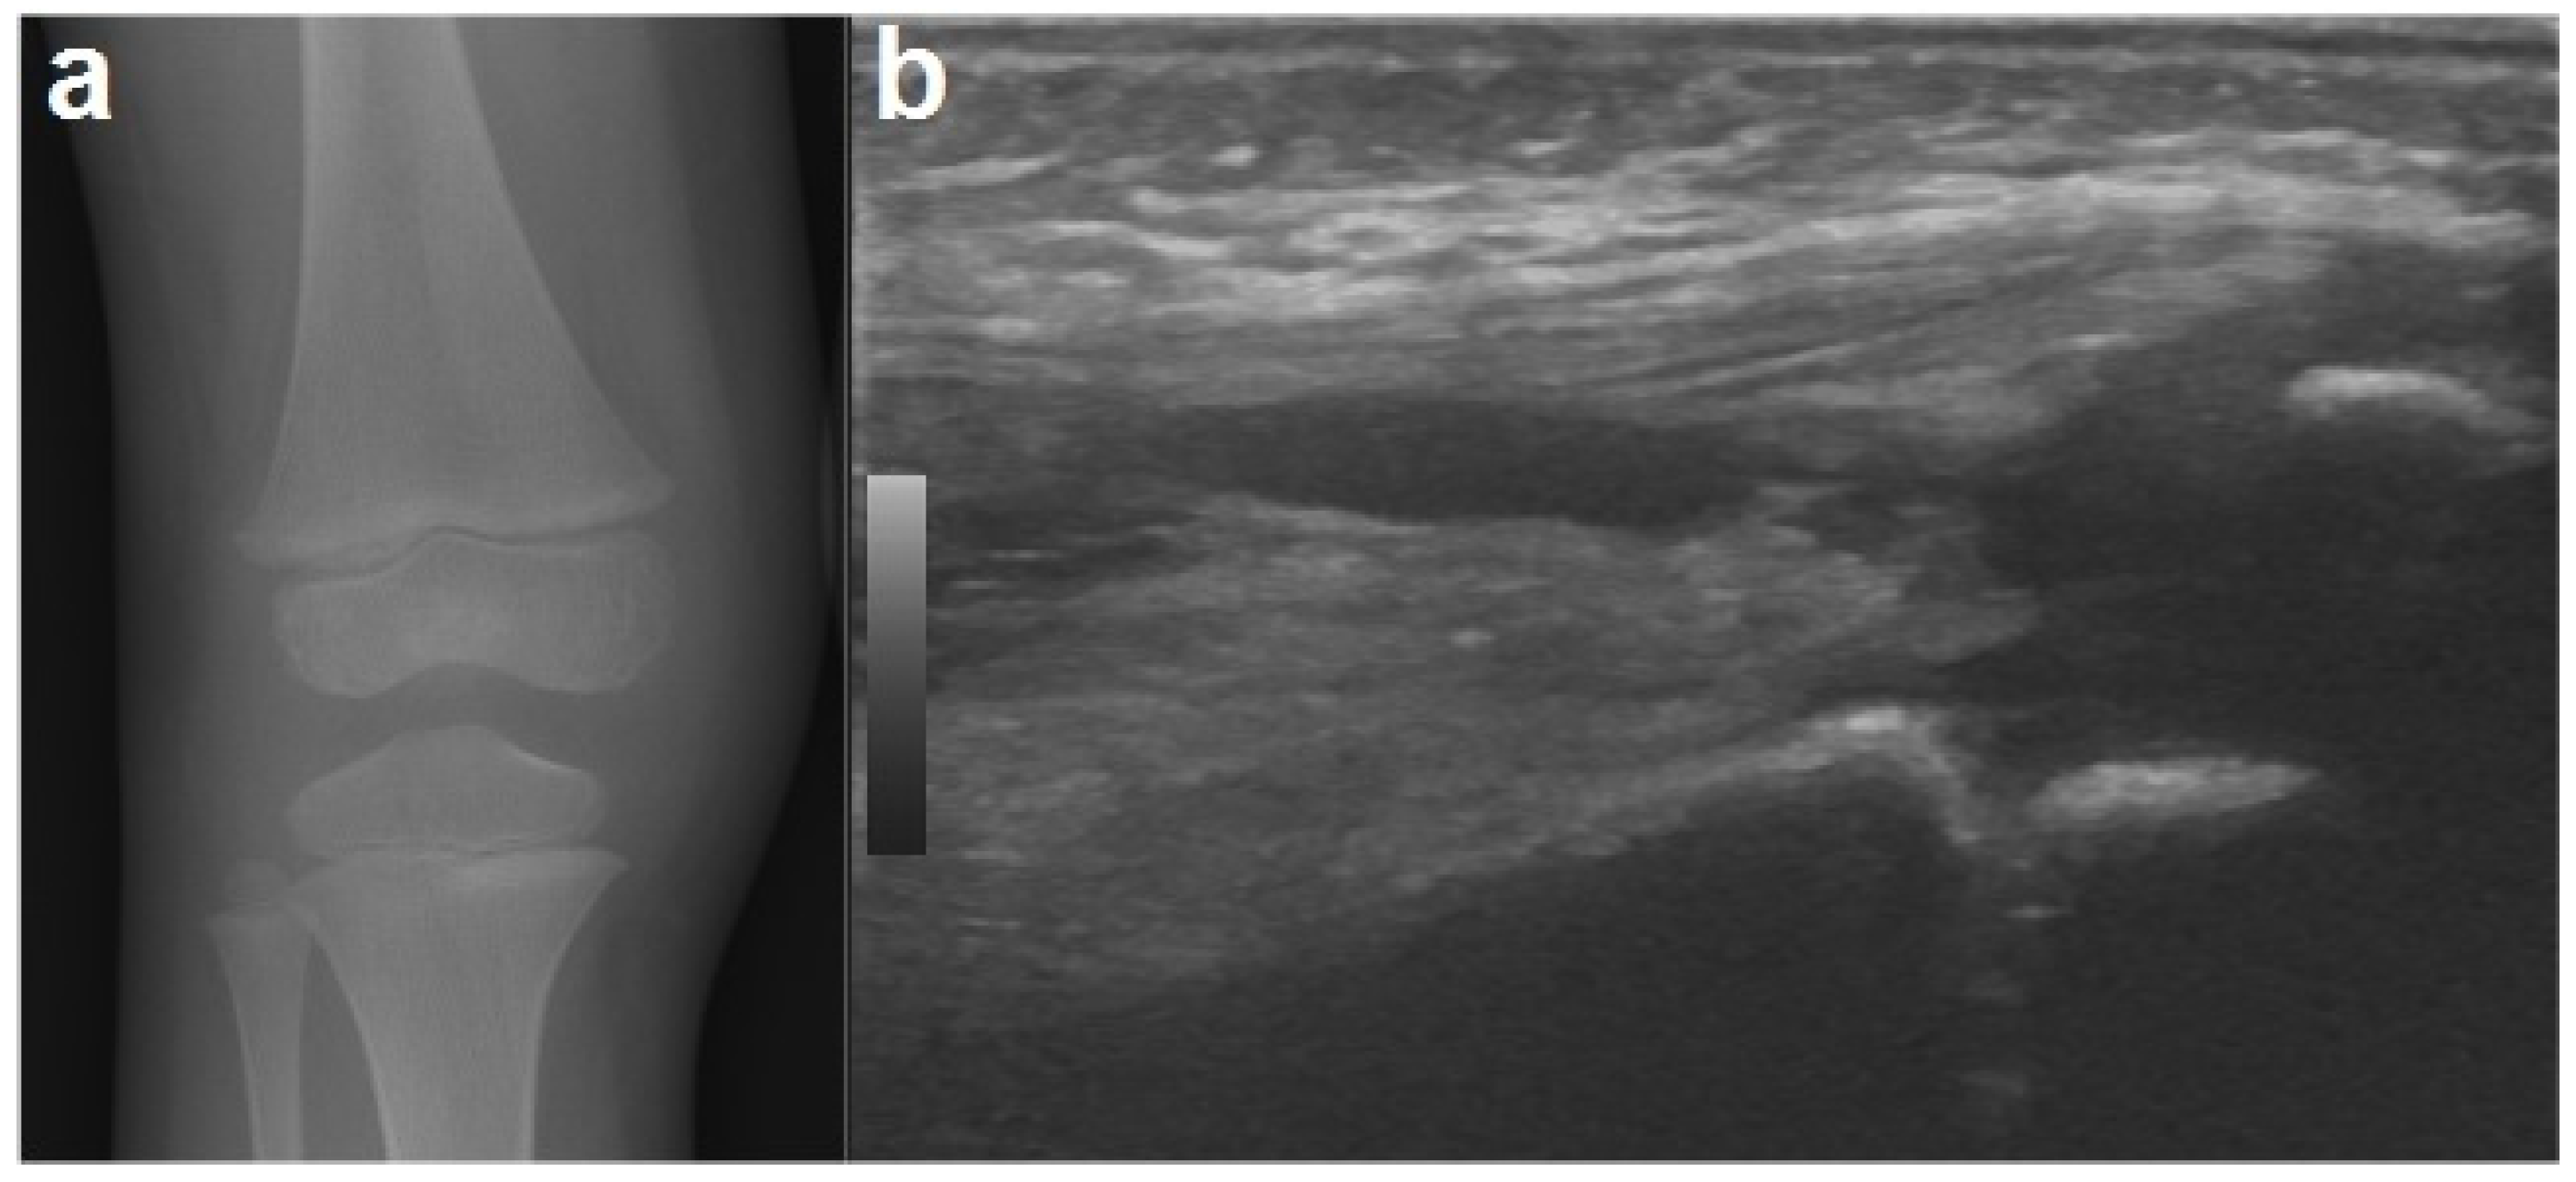

Pediatric Septic Arthritis of the Knee due to Fusobacterium... JBJS Case Connector Pediatric Septic Arthritis Treatment A delay in diagnosis and inappropriate treatment can. Aureus should be treated with drainage or debridement and 14 days of intravenous antibiotics. this clinical practice guideline for the diagnosis and treatment of acute bacterial arthritis (aba) in children was developed by a multidisciplinary panel representing the pediatric infectious diseases society (pids) and the infectious diseases society of america (idsa).. Pediatric Septic Arthritis Treatment.

Children Free FullText Pediatric Septic Arthritis of the Knee Due to a MultiSensitive Pediatric Septic Arthritis Treatment acute septic arthritis in children is an orthopaedic emergency. this clinical practice guideline for the diagnosis and treatment of acute bacterial arthritis (aba) in children was developed by a multidisciplinary panel representing the pediatric infectious diseases society (pids) and the infectious diseases society of america (idsa). A delay in diagnosis and inappropriate treatment can. traditionally, the treatment. Pediatric Septic Arthritis Treatment.